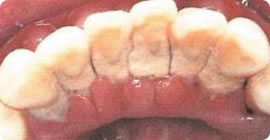

- 歯石もこうなるとブラッシングでは取れません

プラーク(歯垢)や歯石(右写真)はどうしてとらなければいけないの?と疑問に思われる方に、プラークや歯石の為害性や歯周病予防の大切さを知ってほしいです。

プラークは細菌性の沈着物で、歯石はそれが石灰化したもので、それらはむし歯や歯周病を引き起こす因子になります。プラークのなかの細菌は歯に付着した食べかすを利用して酸をつくり、歯の表面のエナメル質を溶かします。そのほか、細菌性のプラークが歯と歯ぐきの間に入りこんで停滞すると歯肉に炎症が起こります。その状態が続くと、細菌のだす毒素で歯根膜(歯と骨をつないでいる線維)が破壊され、さらに奥へと進行します。その結果、歯を支えている骨が溶け、最後には歯を失います。それだけではなく、プラーク中の細菌は、炎症部の血管内に入り込み、血液を通って全身に流れていき、動脈硬化や心疾患のひき金となります。これでプラークや歯石の害の重大さがわかりましたね。日頃から予防することが大切なのです。むし歯も歯周病も、細菌性のプラークが原因で起こります。プラークは患者さん自身の歯みがきで取り除き、歯石はわれわれ専門家である歯科医師・歯科衛生士が取り除きます。お互い力をあわせてがんばりましょう!